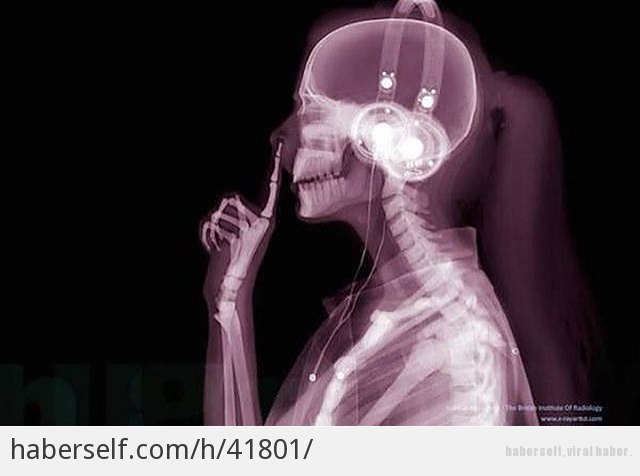

İnsan Vücudunun Farklı Şeyler Yaparken Röntgen Altında Çekilmiş 14 Fotoğrafı

İnsan iskeletinin mucizevi bir yapısı var. Bu mucizeyi X ışınları altından görmek daha kolay ve etkileyici.